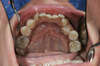

AVANT